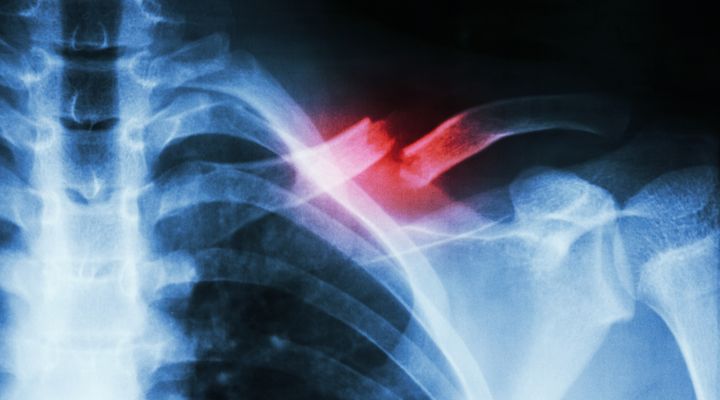

It was 2010 and Cameran was in his sophomore year. As expected, he was already scouting out colleges when disaster struck for the first time. He was making a routine tackle during football practice when he broke his left collarbone. The injury was severe enough that it required surgery and benched him for the rest of the season…

Despite being stuck on the bench, Cameran did manage to push past his impatience and take the time necessary to heal the injury; or so he thought. A few months later, just when he had been given the go-ahead to join wrestling again, he fractured his right collarbone during a match. Now he had two damaged collarbones.